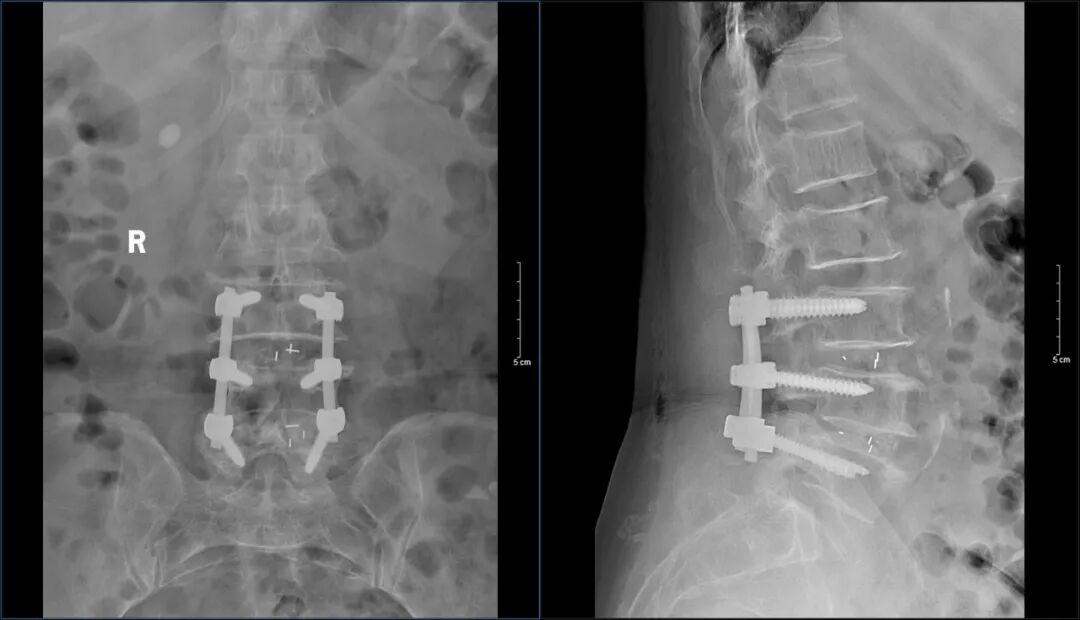

近日,济南南郊医院脊柱外科团队顺利完成又一例经腰椎后路L3/4、L4/5椎管减压+脊髓神经根粘连松解+椎间盘切除+椎间植骨融合钉棒内固定术,术后患者恢复良好,困扰患者多年的腰椎间盘突出症状已经消失。

在明确没有手术禁忌后,经过充分的术前准备,麻醉科团队、手术室团队全部准备就绪,由谭炳毅主任与脊柱外科手术团队顺利完成经腰椎后路L3/4、L4/5椎管减压+脊髓神经根粘连松解+椎间盘切除+椎间植骨融合钉棒内固定术。术中分别在对应位置置入螺钉固定椎体,切除肥厚韧带、退变的椎间盘和髓核,向后挤压突出椎间盘硬膜囊及神经根开窗减压,在椎间隙内植入自体骨粒和填充自体骨粒的椎间融合器,手术进展十分顺利。